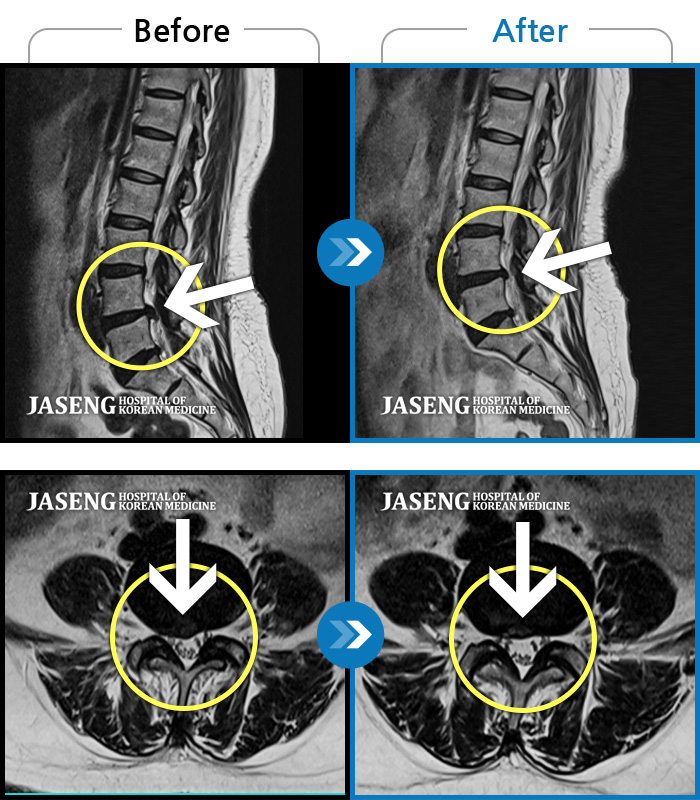

허리디스크

광주 · 김동은 원장

좌측 골반 및 종아리부터 발까지 이어지는 저림과 통증으로 내원하셨습니다.

촬영시기

2023.10.03 ~ 2025.08.14

2025.08.22